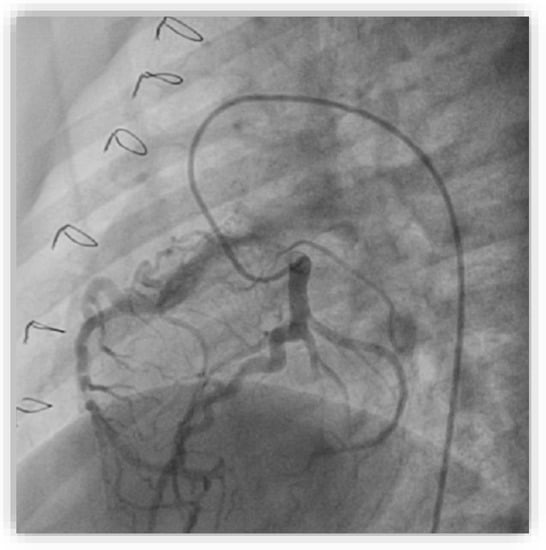

2. Case Report #1

| Invasive coronarography |